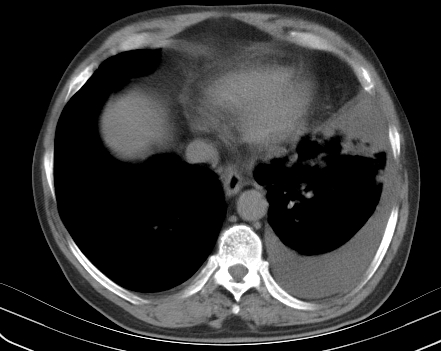

以下是引用老爱克斯新网客在2008-7-31 6:30:00的发言:[br]左肺上叶大片状病灶,左肺上叶支气管狭窄呈鼠尾状,左肺门增大,纵隔内见肿大淋巴结,左侧胸腔积液,余肺清晰。左肺中心型肺癌淋巴结转移,

以下是引用zjzjr在2008-7-31 8:45:00的发言:[br]考虑左侧中心性肺癌伴阻塞性肺炎,左肺上叶肺不张,纵隔淋巴结转移;左侧胸腔积液。建议行纤支镜检查。

以下是引用zjb在2008-7-31 6:32:00的发言:[br]左侧中心性肺癌 阻塞性肺炎 肺不张 胸腔积液 建议气管镜

以下是引用sdzyy在2008-7-31 8:47:00的发言:[br]病灶较治疗前有所进展,胸水增多, 左侧中心性肺癌 并 阻塞性肺炎 肺不张 胸腔积液 可能性大; 建议气管镜检查。 [br] [br]